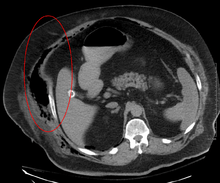

Computed tomography (CT scan) is able to detect about 80% of cases while MRI may pick up slightly more.[13]